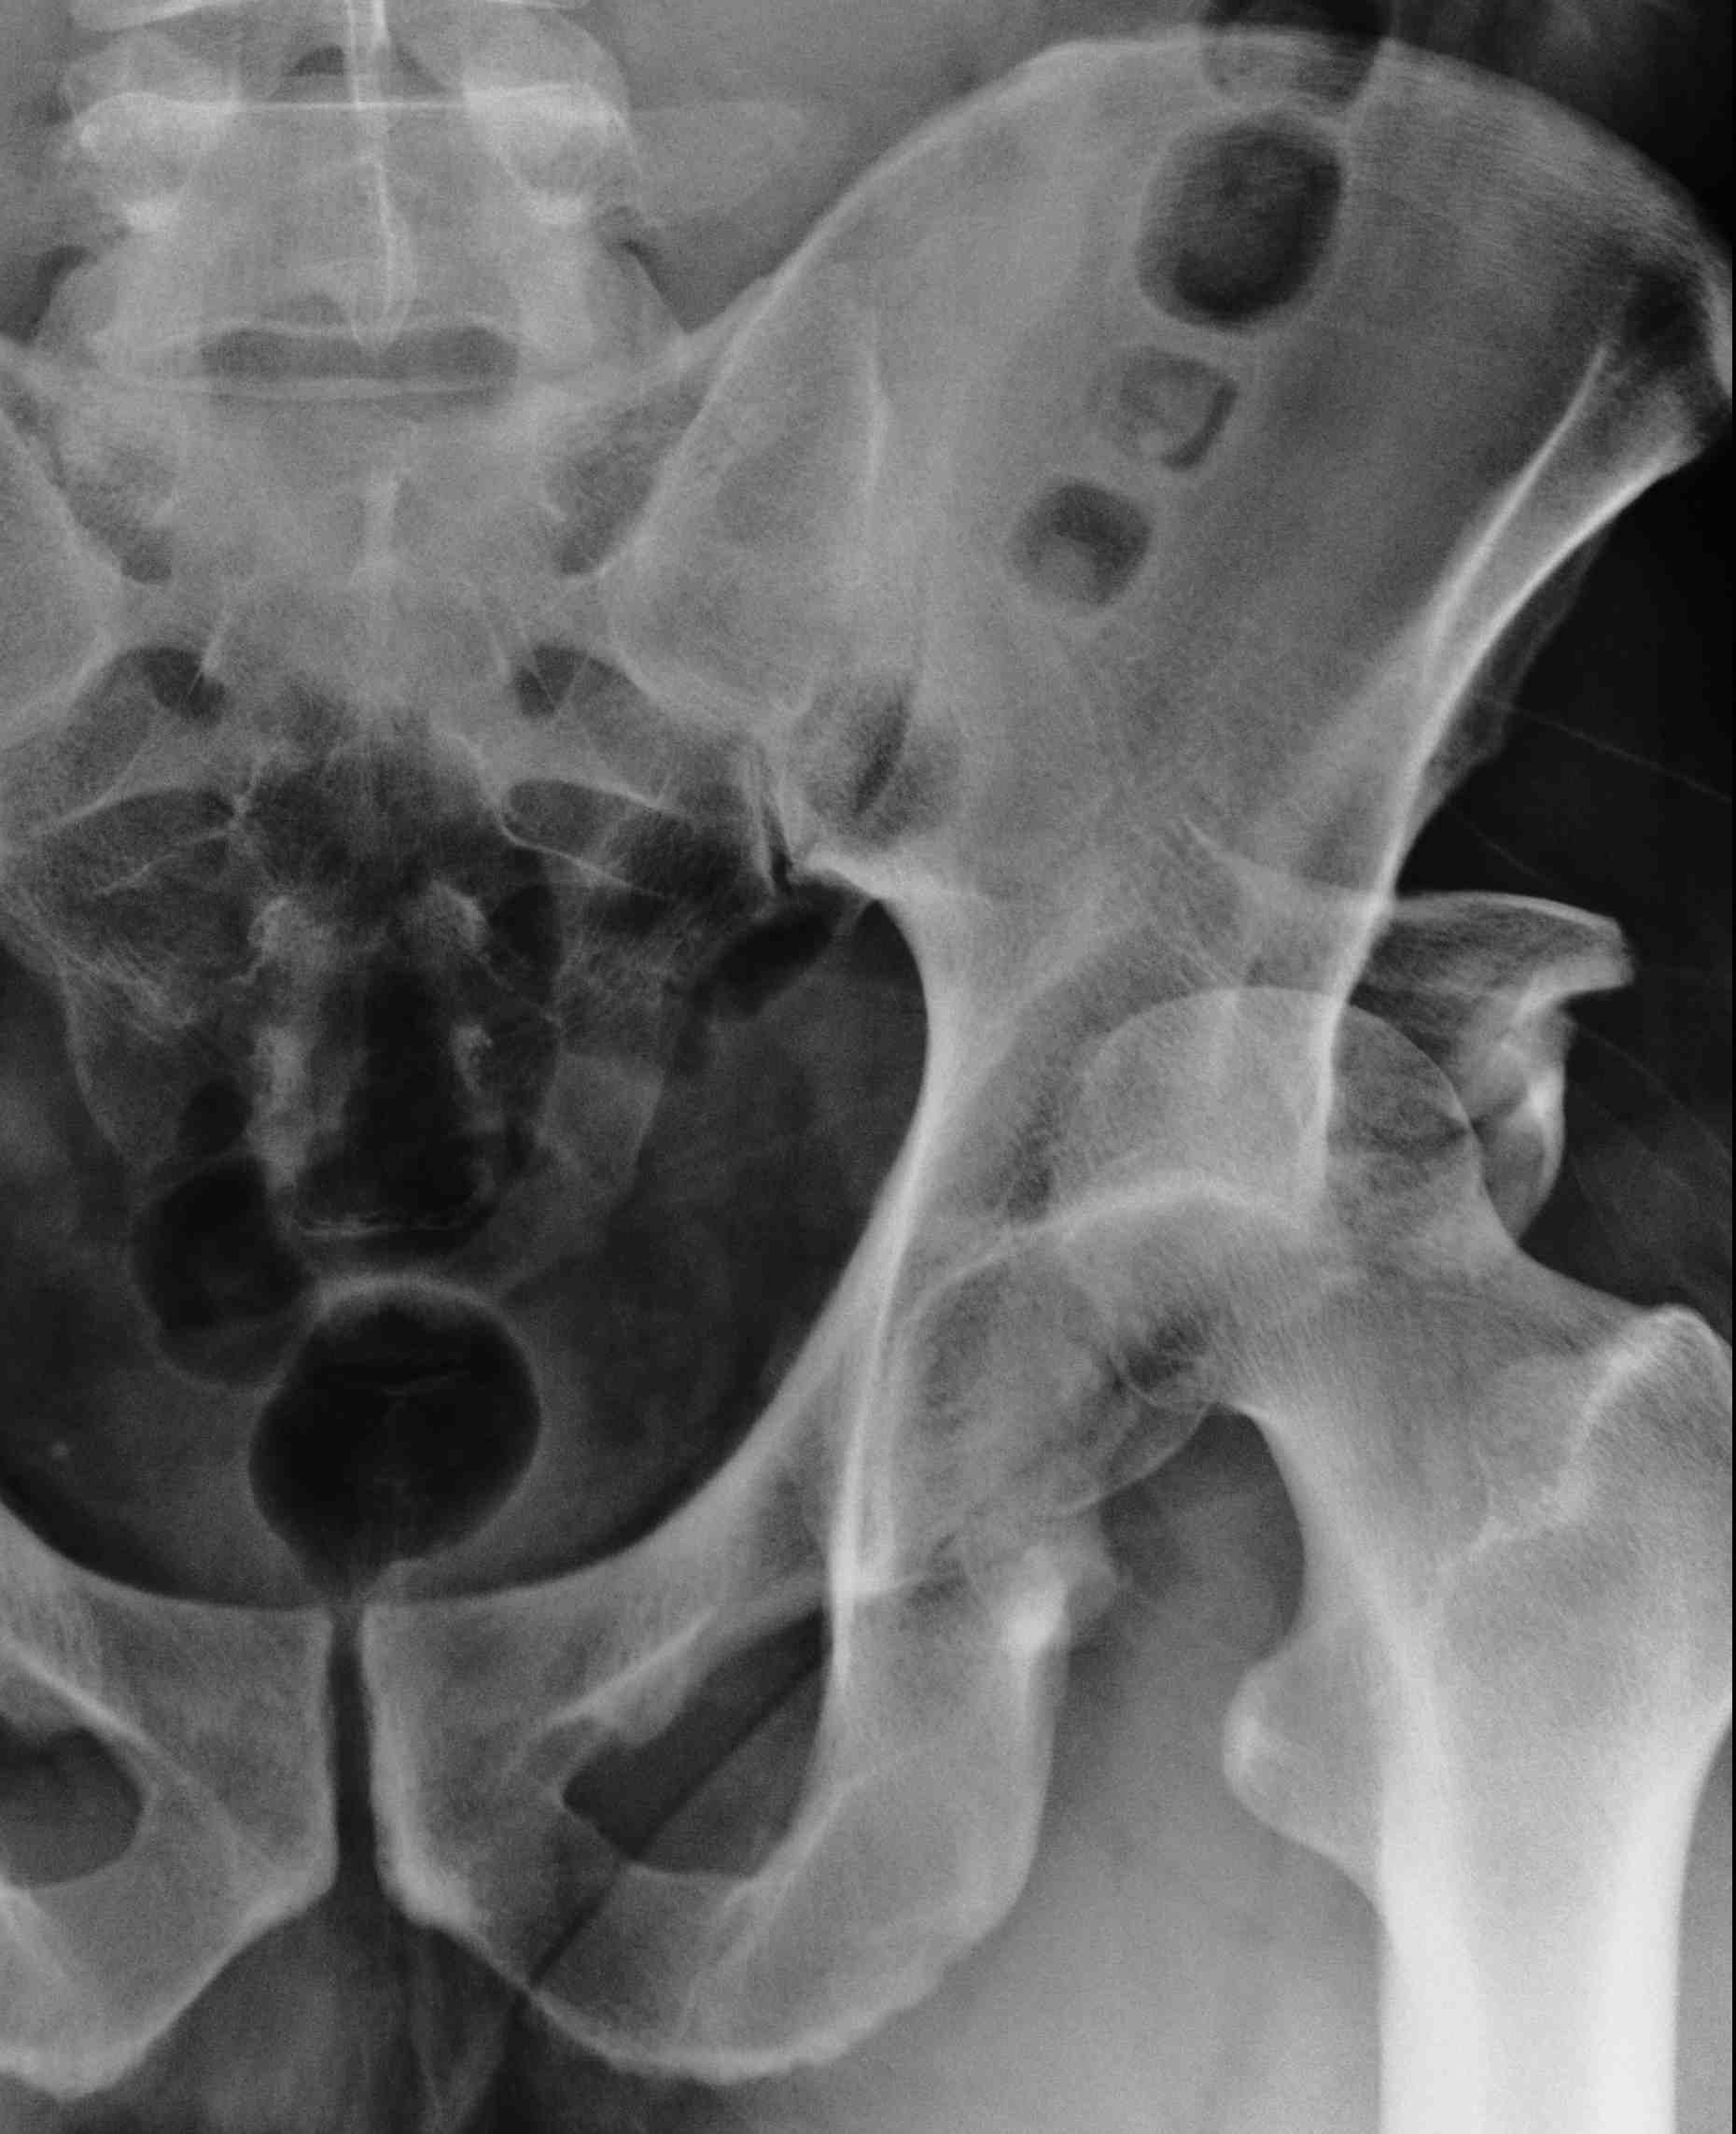

Acetabular fracture

Femoral head fracture / Pipkin fracture

Classification

3. Posterior

Posterior dislocation

- leg shortened, flexed, adducted & internally rotated

- head small on xray

2. Assess stability

Posterior wall fracture > 40%

- need ORIF for stability

Posterior wall fracture < 40%

- can be unstable

- EUA after reduction to assess stability

- should be able to flex to 90o and some IR without instability